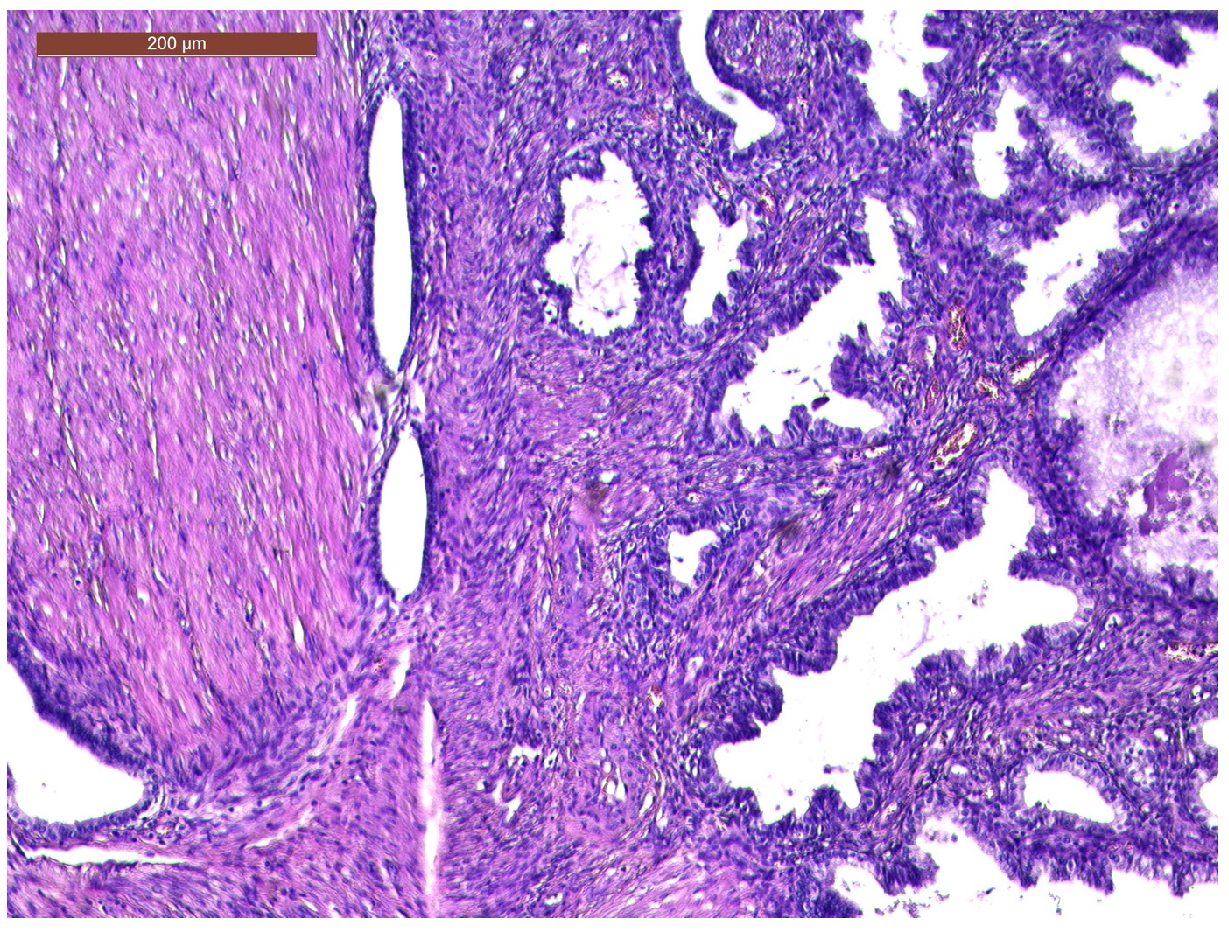

In the vagina, occupying the entire cavity, a mass was found, which bled on touch, presenting a pedicle originating above the cervix. We performed the excision of the mass using forceps, scissors, and a suture of the visible pedicle (Figure 3).

The close examination revealed a tumoral mass measuring 4.9/4.6/4.5 cm, with an irregular bosselated surface. The cut section of the tumor showed a white-grey surface with microcystic areas and a hemorrhagic gelatinous content.

Figure 4. Endometrial glands with lymphoid follicles and associated smooth muscle fibers (HE × 10).

Figure 5. Thick bundles of smooth muscle fibers interspersed with endometrial areas containing irregularly oriented glands and dense cellular stroma (HE × 10).